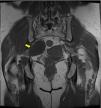

MethodsWe conducted a retrospective analysis of 19 cases of patients with neurogenic tumors in the sacral area who were diagnosed and underwent surgery at our center. Of them, 8 were male and 11 were female. They had a mean age at diagnosis of 51 years (with an age range of 25–78 years). Six patients were asymptomatic and were diagnosed incidentally, while the majority (11 patients) presented with lumbar pain accompanied by other symptoms: pain radiating to the legs, pelvic pain, sensory alterations and loss of strength in the legs. Two patients presented with another primary symptom on diagnosis: pain in the pelvic region and in the left leg. All patients underwent a least one imaging test (MRI/CT scan). Nine patients had tumors limited to the sacrum or with subsequent spread, with surgery via the posterior route. In 6 cases, an exclusively anterior approach was employed owing to the pre-sacral location of the tumor; 4 cases required both an anterior and posterior approach.

ResultsThe 6 patients who were asymptomatic at diagnosis continued to have no symptoms after surgery. In 8 patients, symptoms resolved after surgery, and at discharge 4 had pain in the lumbar region or legs, which improved in subsequent consultations. One patient had symptoms consistent with motor and sensory deficit in the right leg deriving from impairment of the external popliteal sciatic nerve. The mean follow-up period was 69 months (6–178 months). Histologically, 17 cases were classified as schwannomas, one case was classified as neurofibroma, and one case was classified as neurofibrosarcoma, which received radiotherapy. Three patients with benign histologies had further surgery for local recurrences.

ConclusionsWhen selecting the approach, the large size that these tumors can reach, their relationship with structures, and their anterior or posterior spread should be taken in to account. Resecting the tumor mass as much as possible provides greater benefit to the patient, as this decreases the odds of tumor recurrence without increasing intraoperative and postoperative complications when multidisciplinary teams are also used.